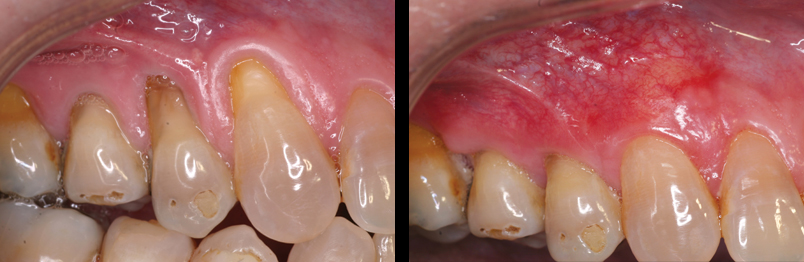

At times tissue (gum) around the teeth can strip away. This stripping process is called “recession”. Once a recession begins, it tends to progress with time. A recession can jeopardize the retention of your teeth and in certain situations cause a cosmetic problem. There is a treatment option for each of these issues. A i) Gingival Graft focuses on

functional issues while an ii) Connective Tissue Graft focuses on cosmetic issues.

Gingival Graft:

The conventional treatment for recession is the Gingival Graft. The procedure is designed to enhance and reinforce thinning tissue with more durable or …”beefy” gingiva.

Connective Tissue Grafts:

In certain situations, gingival recession can cause a cosmetic problem. The procedure of choice for cases like this is the Connective Tissue Graft. This procedure not only “beefs up” the supporting tissues around a tooth but has the added benefit of cosmetic root coverage.